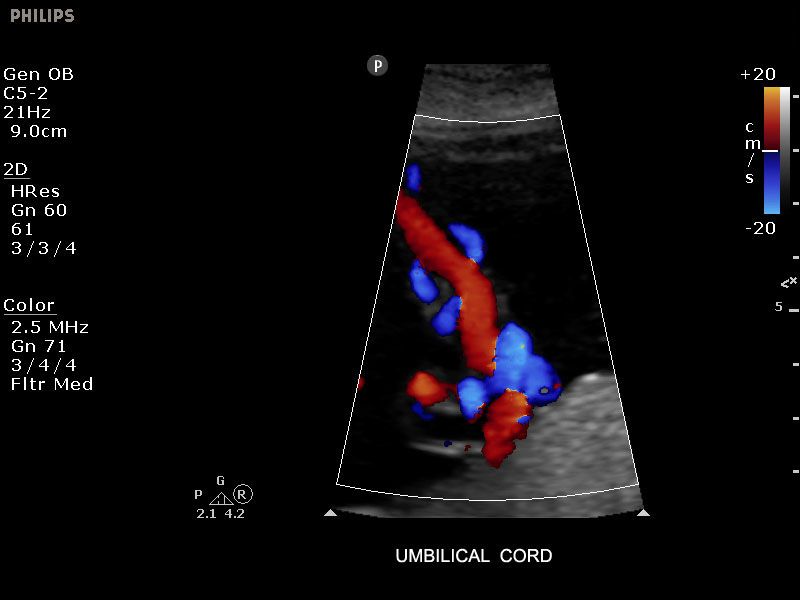

Erstellen Sie hochwertige 2D-, Farb- und Dopplerbilder einfach per Knopfdruck über IScan. Oder nutzen Sie die bewährte SonoCT- und XRES-Bildverarbeitungstechnologie zur Verbesserung der Bildqualität. Die integrierten, an Ihren Arbeitsablauf angepassten SmartExam-Protokolle helfen Ihnen dabei, schnell und effizient zu arbeiten.